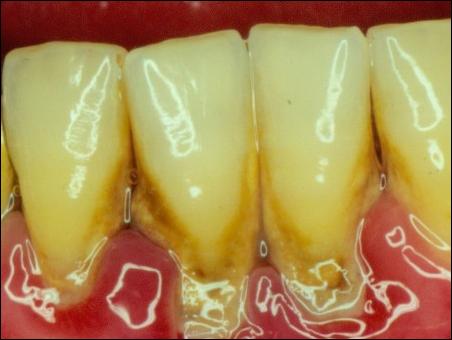

掛滿了結石的牙齦組織紅腫

潔完牙后,牙齦組織恢復成粉白色,不再充血發(fā)炎